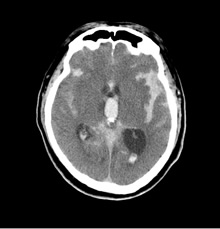

突然、頭を抱えて頭痛を訴えた後で倒れてしまった人を目の前にしたら、くも膜下出血と決めて救急車を呼ぶべきであるぐらい、特徴的な症状と言えます。くも膜下出血では、脳表面のクモ膜下腔に出血がみられ特徴的なCT所見を呈します。出血が軽度でCT上、特徴的な所見が見つからない場合、腰に長い注射針を穿刺し、脳脊髄液に血液の混入があるかどうかを確かめる必要があります。経験のない突然の強い頭痛が見られた場合には、念のため医療機関の受診をお勧めします。